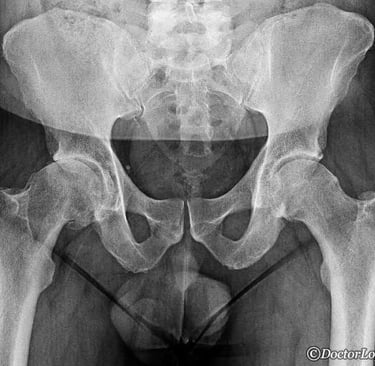

Diagnóstico

El diagnóstico se basa en una historia clínica detallada, la exploración física y estudios de imagen.

Las radiografías permiten observar el grado de desgaste del cartílago y la forma de la articulación.

En algunos casos, se pueden solicitar resonancia magnética o tomografía para evaluar estructuras blandas o alteraciones más sutiles.